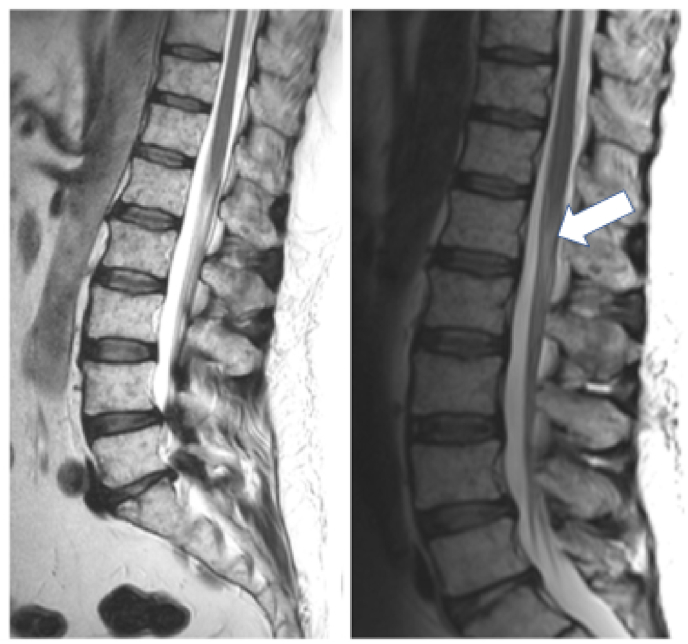

Material and methods: In this paper we report the case of a 53-year-old man who was, in the course of his treatment for acute lymphoblastic leukemia (ALL), inadvertently injected with vindesine intrathecally. The patient survived following aggressive and invasive treatment, which included irrigation of the CSF via external ventricular and lumbar drains. We also conducted a systematic review of similar published cases.

Result: A total of 31 cases with intrathecal inadvertent vinca alkaloid injection were identified. Including the case described in this report only two patients were injected with vindesine (n = 2, 6.5 %), all other received vincristine. Only 6/31 (19.4 %) patients survived the acute phase of the vinca alkaloid intoxication. 6/15 (40.0 %) patients receiving some sort of CSF irrigation survived (cf. 0/12 without irrigation therapy). All survivors were left with very significant neurological deficits.

Discussion and conclusion: The combined evidence suggests that intrathecal administration of vincristine is universally fatal without treatment, while CSF irrigation carries a chance of survival. Patients are, however, left with severe neurological deficits such as paraplegia.